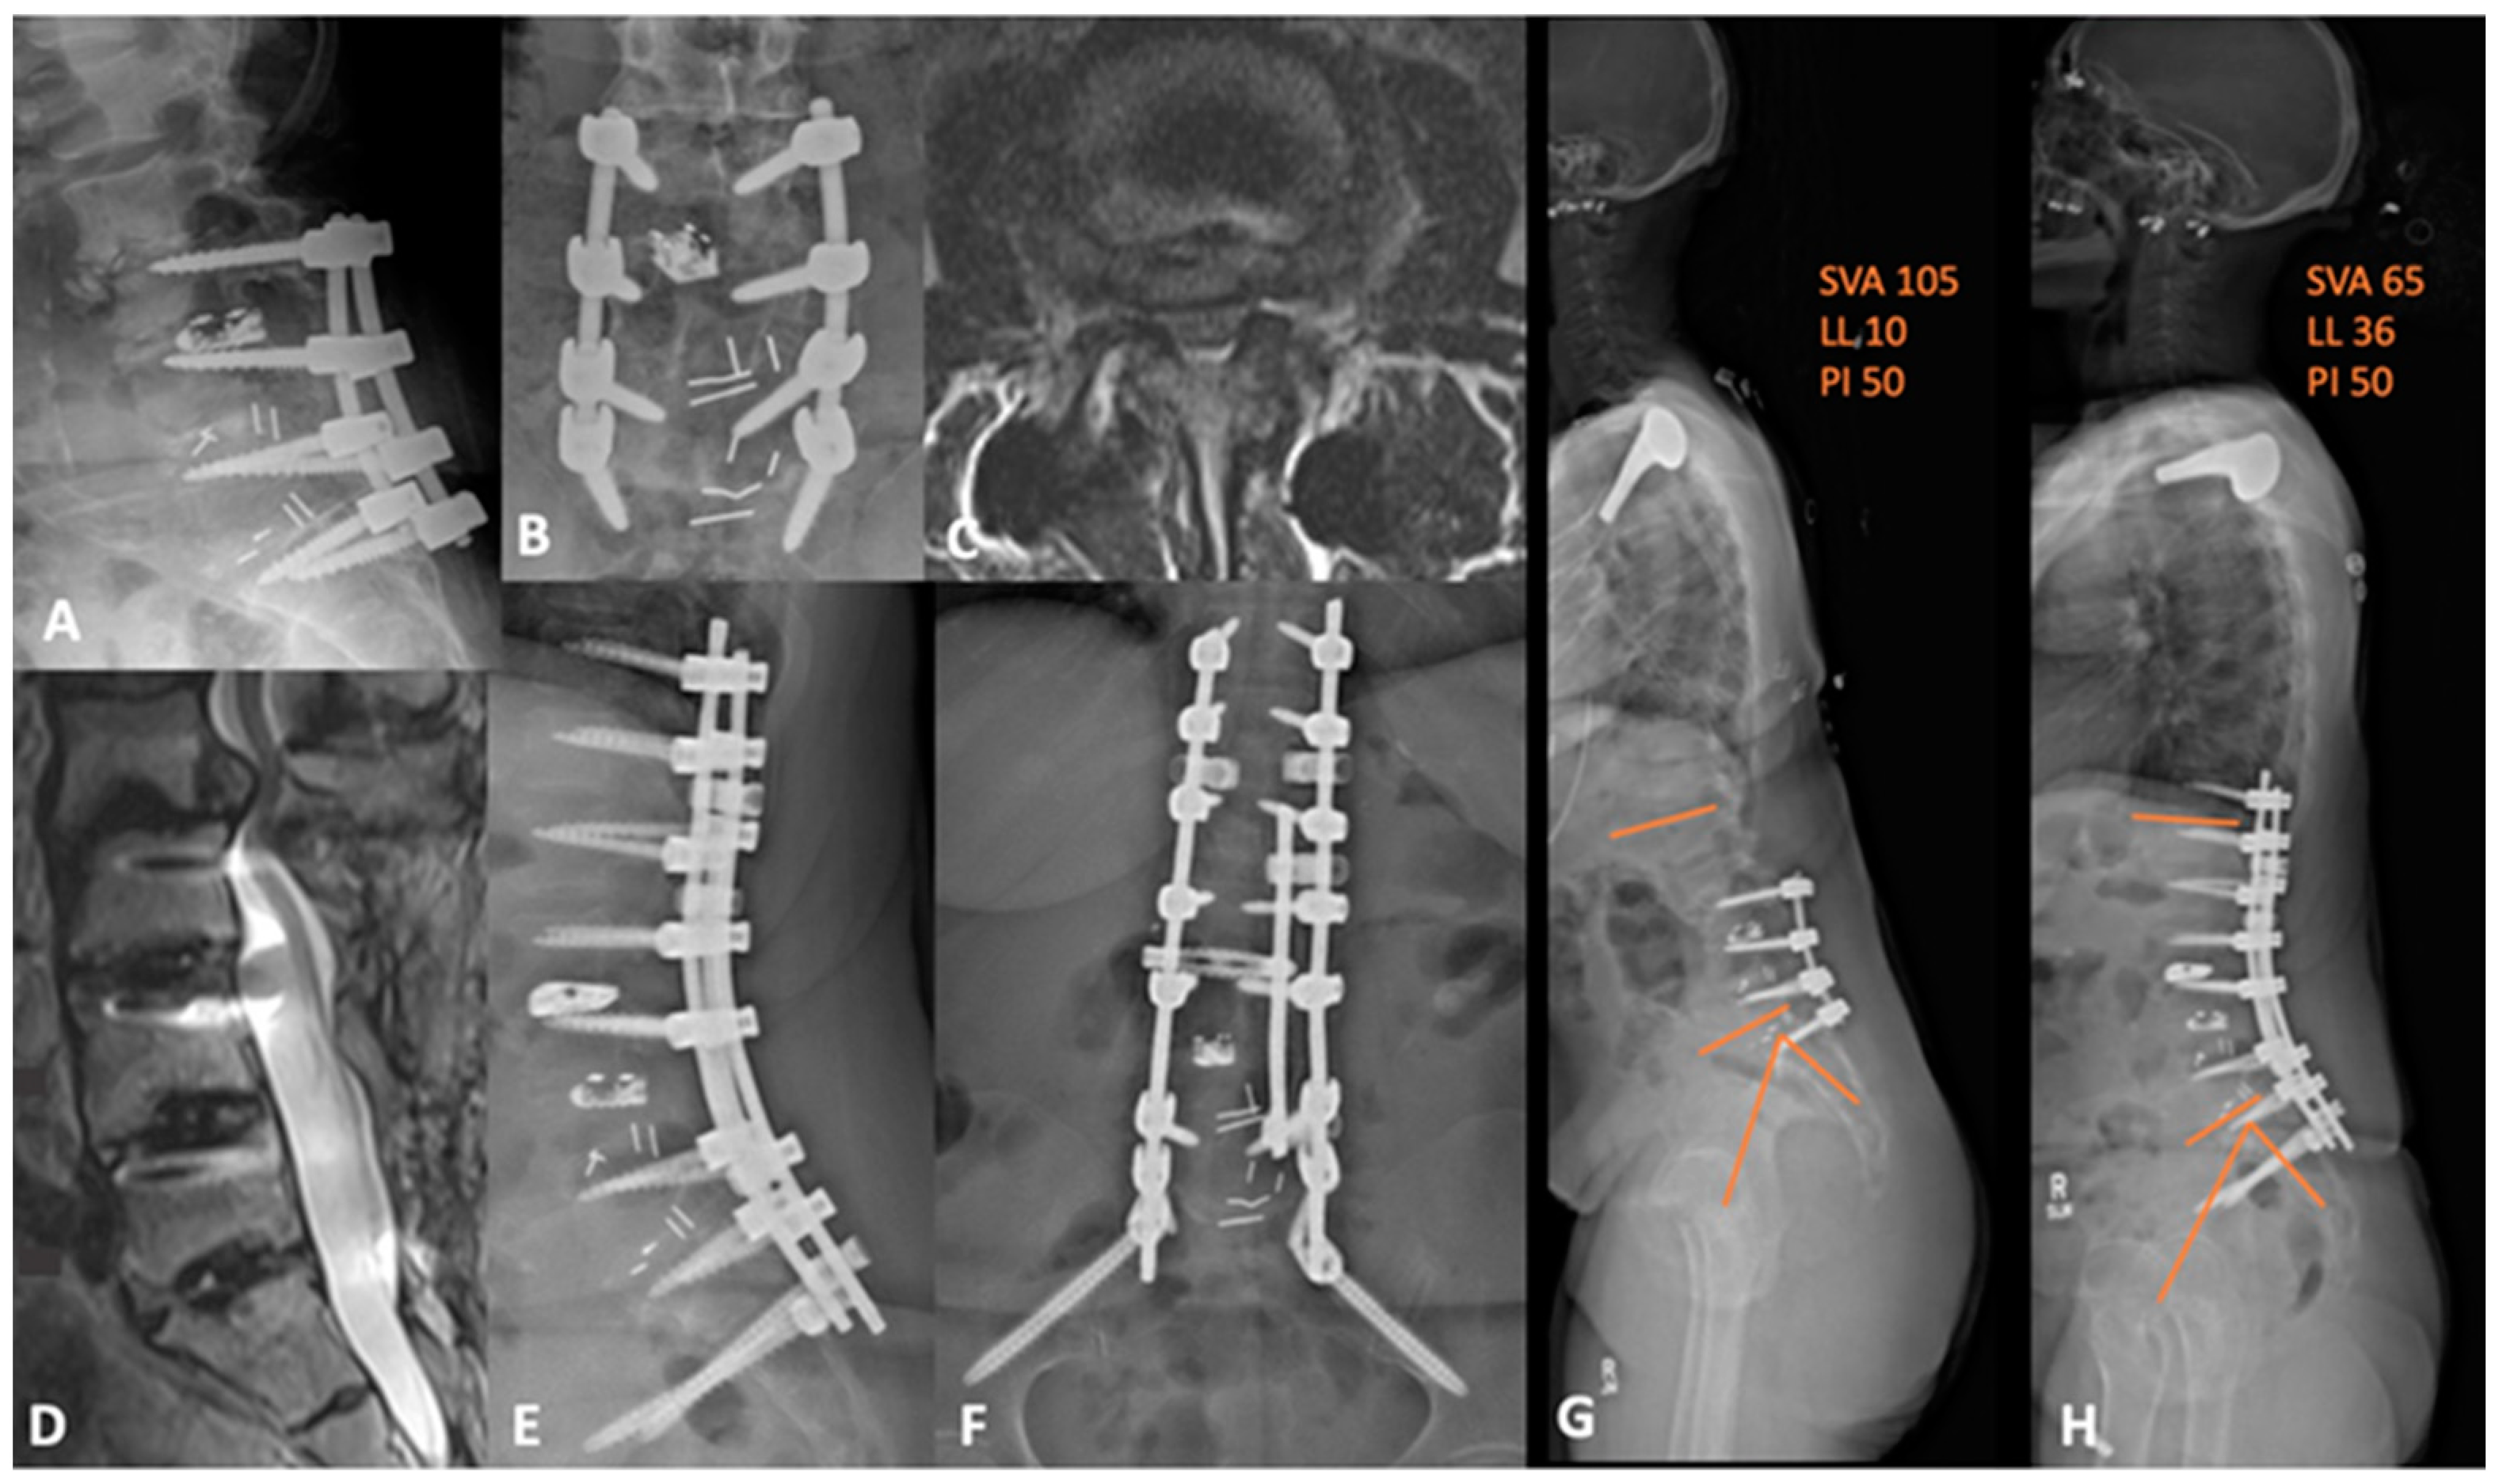

Below, the authors present two representative deformity cases. Case 4 is a 60-year-old female, with two previous operations, who was referred to us from another institution. She has a remote history of L3-4 decompressive laminectomies and, most recently, L3-S1 TLIF 3 years prior to presentation. She presented complaining of severe low back pain with radiation to both thighs anterolaterally. Her imaging was notable for L2-3 ASD, anterolisthesis, and positive sagittal imbalance with a PI-LL mismatch—flat-back deformity. We therefore decided on L2-3 PTP lateral interbody fusion, L2-3 posterior column osteotomy (PCO), L4 PSO, and T11-pelvis fusion extension. The postoperative course was uneventful, and the patient had substantial symptomatic relief with improved sagittal balance and a PI-LL mismatch of 14, compared to 40, preoperatively, as shown in Figure 6.

Figure 6. (A,B) preoperative lateral and AP lumbar X-rays demonstrating the advanced degenerative changes at L2-3 with grade 2 anterolisthesis. (C) axial and (D) sagittal T2-weighted MRI showing the adjacent segment disease at L2-3 with severe central and lateral recess stenosis. (E,F) lateral and AP lumbar X-rays of the postoperative construct with apparent deformity correction. (G) preoperative and (H) postoperative whole-spine films demonstrating an improvement in sagittal balance and global lordosis. SVA = sagittal vertical axis; LL = lumbar lordosis; PI = pelvic incidence.